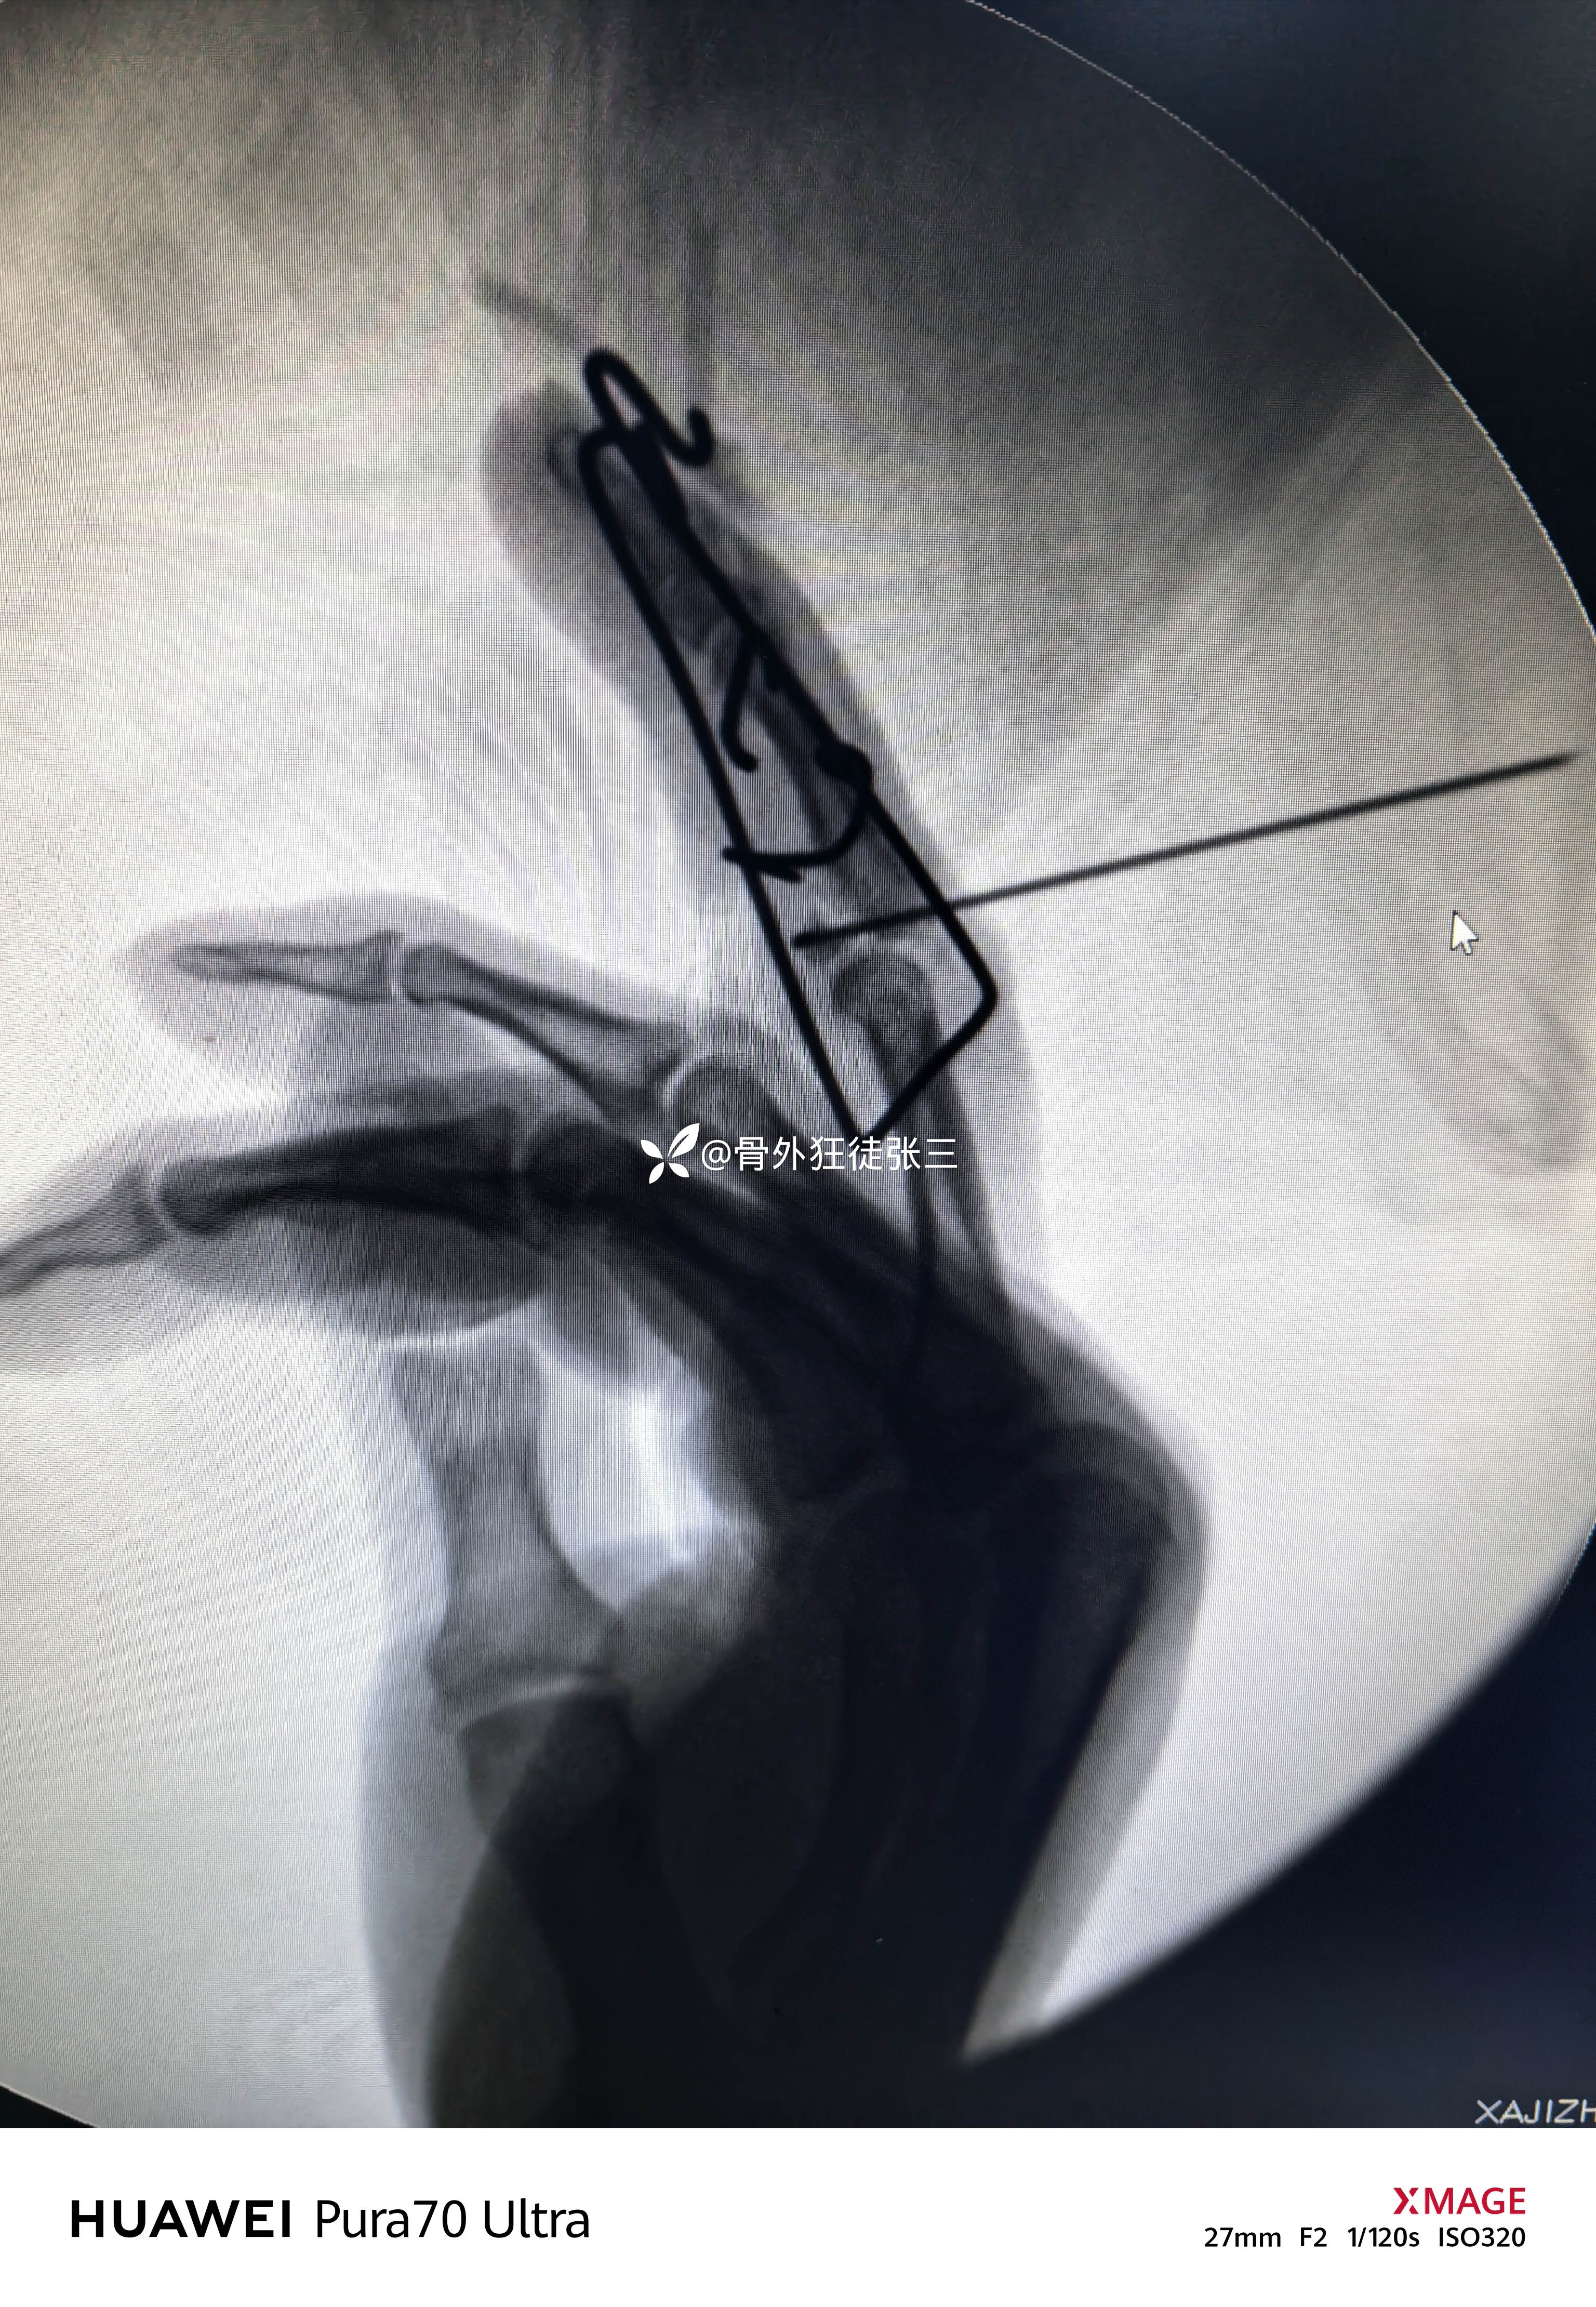

掌侧小Z切开

暴露指浅屈肌腱止点骨块

清理折端和关节

复位骨折

从掌侧in-out-in穿出

折弯阻挡骨块

透视发现骨块无法复位

脱位无法纠正

于是乎

先复位脱位,再透视

发现关节不稳无法维持复位

只能克氏针固定关节

保持复位

再次用阻挡克氏针复位骨块

透视发现骨块复位

关节复位